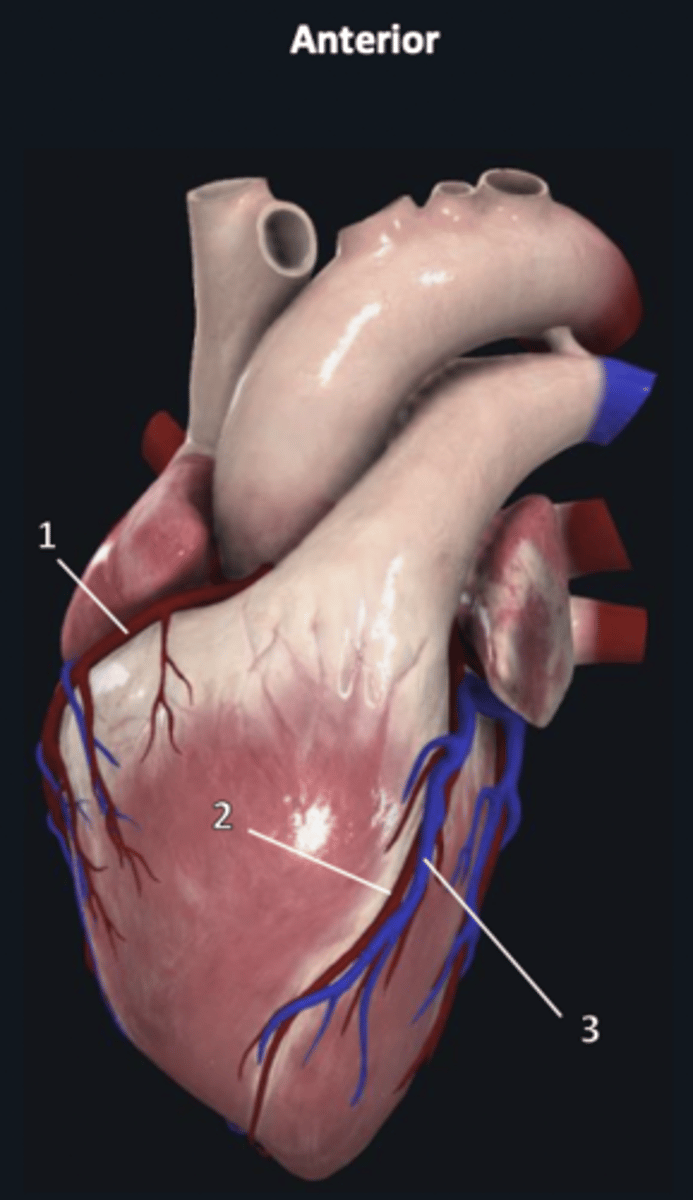

right coronary artery

1

anterior interventricular artery

2 (red)

great cardiac vein

3 (blue)

anterior interventricular artery

2 (red)

great cardiac vein

3 (blue)